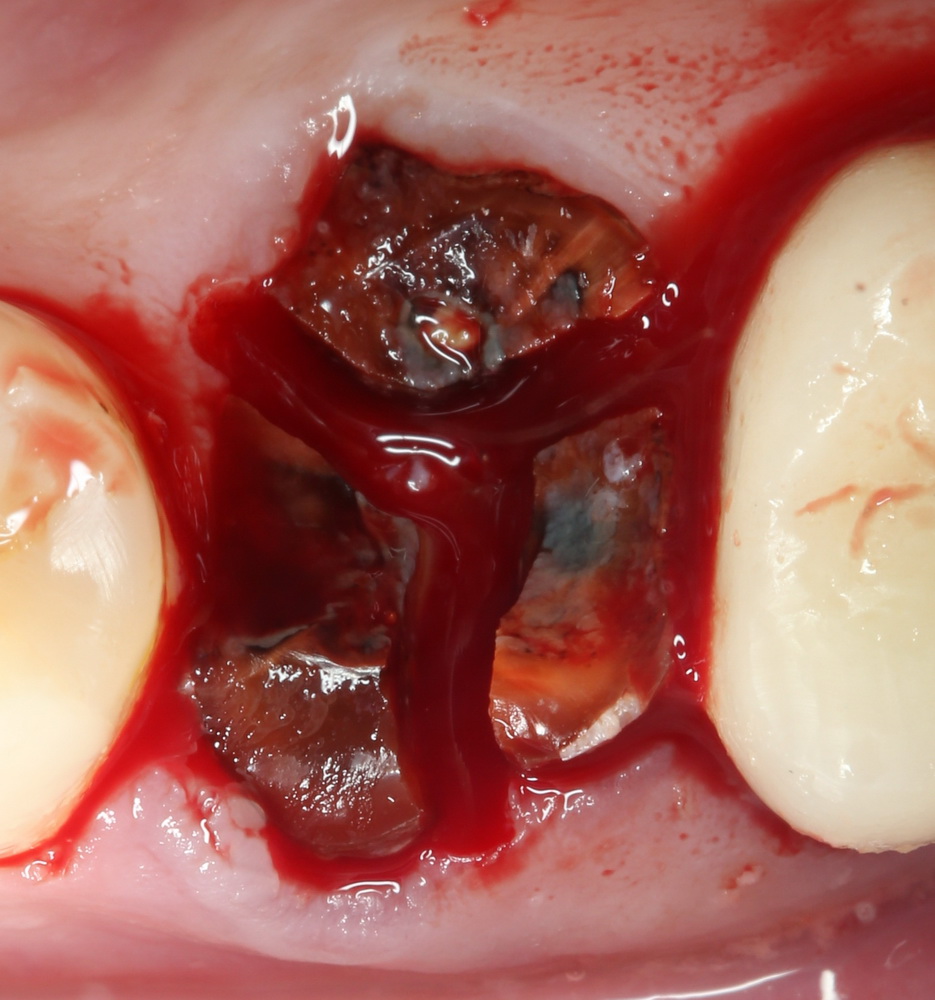

При очередной ортопантомограмме выявились две огромные гранулемы в области 45 и 47 зуба. Лечение — без шансов, зубы придется удалить. Причем, немедленная имплантация не представляется возможной — слишком уж большой размер гранулем.

Гранулема настолько большая, что ее видно из лунки:

Аккуратно ее удаляем. Приходится пожертвовать межкорневой перегородкой:

После чего можно заняться лункой зуба #45. Там тоже гранулема. Немаленькая: